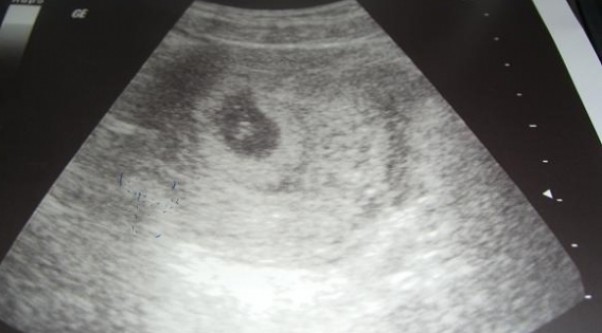

Drugi bobasek. PIERWSZE ZDJ Z USG

Witajcie, Nazywam się Asia mam prawie roczną córeczkę Zuzie, miesiąc temu dowiedziałam sie że zostane drugi raz mamą. :)